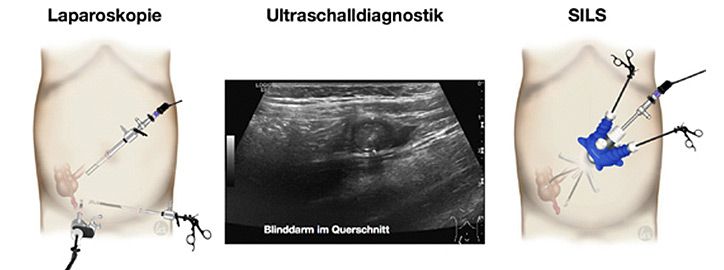

Diagnostik

Die Diagnose der Appendizitis wird durch die ärztliche Untersuchung gestellt, allerdings ergänzt durch Ultraschall-, Blut- und Urinuntersuchungen.

Therapie

Unbehandelt kann die Entzündung bis zum Durchbruch (Perforation in die freie Bauchhöhle) führen. Wir empfehlen die operative Blinddarmentfernung (Appendektomie), die in unserer Klinik minimal invasiv durchgeführt wird verbunden mit zahlreichen Vorteilen dieser Methode.